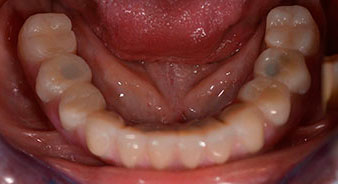

La patiente âgée de 64 ans présente une denture résiduelle des dents 38, 33 et 43 et une prothèse amovible mandibulaire stabilisée par crochets (Fig. 1 et 2).

Un CT Scan à faisceaux coniques tridimensionnel (CBCT, Planmeca) a été réalisé au préalable afin de réduire les risques. Il a révélé une qualité et une quantité d'os disponible suffisante pour l'intervention chirurgicale et la restauration immédiate par la méthode All-on-four. En suivant le protocole de ce concept, les implants sont insérés au niveau de 35, 32, 42 et 45 en inclinant les implants distaux jusqu'à 45°, le profil d'émergence se déplace ainsi vers l'arrière et produit un polygone de stabilisation plus large (Fig. 3).

Après ostéointégration, l'empreinte finale des implants a été effectuée et la prothèse finale a été fabriquée en conséquence (Fig. 19 et 20). À cette étape, le praticien et le patient ont pu décider ensemble d'utiliser une facette dentaire en céramique ou en acrylique et une armature en zircone ou en métal. Dans ce cas, l'équipe du Dr Pascu a opté pour une facette dentaire en acrylique en raison du pronostic incertain de la denture maxillaire et du fait que la dent 24 est extrusée. Ce type de facette est plus facile à ajuster et peut donc être modifiée selon la nouvelle situation maxillaire.